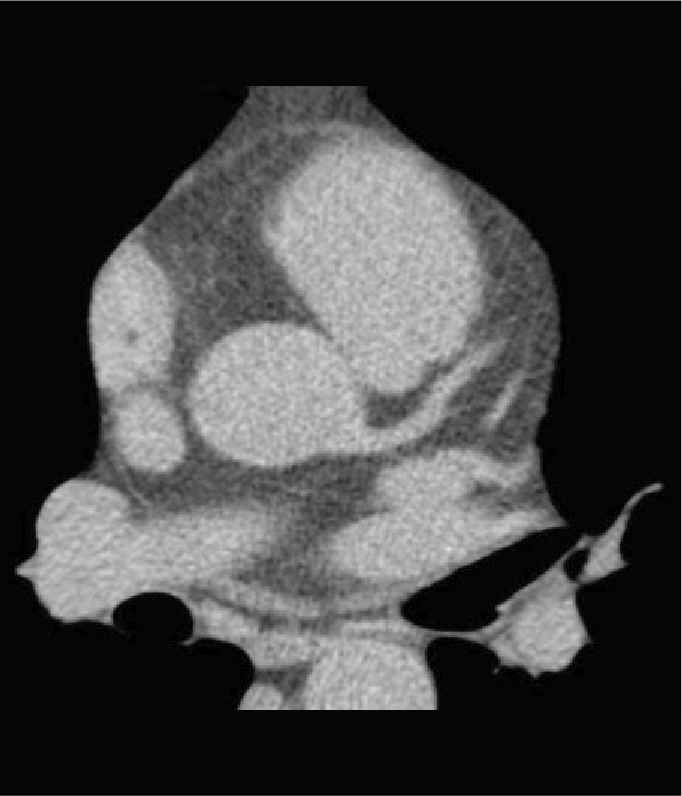

Tomografía cardiaca

Este estudio es adquirido con un tomógrafo de alta velocidad y baja radiación que permite evaluar las arterias coronarias y demostrar la ausencia o la presencia de placas ateromatosas, que son las que ocasionan un infarto (enfermedad arterial coronaria). Mediante la emisión de rayos X es posible obtener imágenes bidimensionales y tridimensionales del exterior y del interior de las arterias coronarias, del corazón y de la función cardiaca.

Una modalidad de la tomografía cardiaca muy utilizada hoy día es el índice de calcio coronario que es útil para identificar oportunamente la presencia de calcio que se asocia con las placas de ateroma que obstruyen tus arterias y ocasionan un infarto. Este estudio se adquiere en menos de un minuto y no se necesita utilizar medio de contraste.

El calcio que se deposita en las arterias coronarias es la “primera señal” que podemos medir antes de que aparezcan los síntomas de la enfermedad y en conjunto con las indicaciones de tu médico, podrás prevenir la progresión de la enfermedad e incluso un infarto.

Cuando es necesario hacer una evaluación mas precisa de tus arterias coronarias la tomografía cardiaca permite, mediante la inyección de contraste por una vena del brazo, estudiar el interior de las arterias y demostrar si existen o no placas que impiden el paso de sangre hacia el corazón, a esta modalidad de la tomografía cardiaca le conocemos como angiotomografía coronaria, que se adquiere en 30 a 60 minutos, y es hoy día el estudio mas confiable para evaluar en forma no invasiva las arterias que nutren al corazón y que cuando se enferman pueden ocasionarte un infarto.

Existen otras indicaciones de la tomografía cardiaca que permiten evaluar las válvulas del corazón y de los grandes vasos como la aorta.